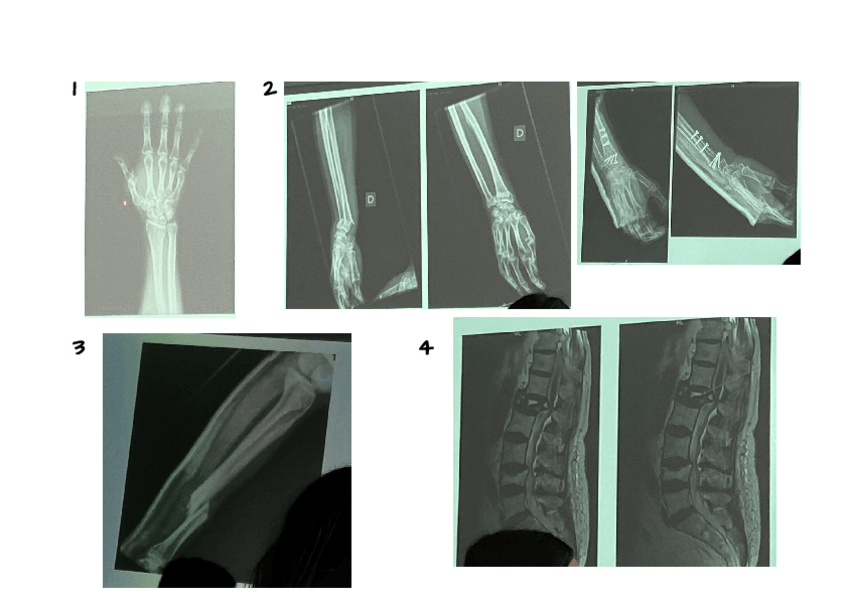

He publicado nuevos ejercicios de 2º Cuidados de Enfermería en Procesos Osteoarticulares: radiografias.pdf

2 páginas

He publicado nuevos apuntes de 2º Cuidados de Enfermería en Procesos Osteoarticulares: RXS-osteo.pdf

21 páginas